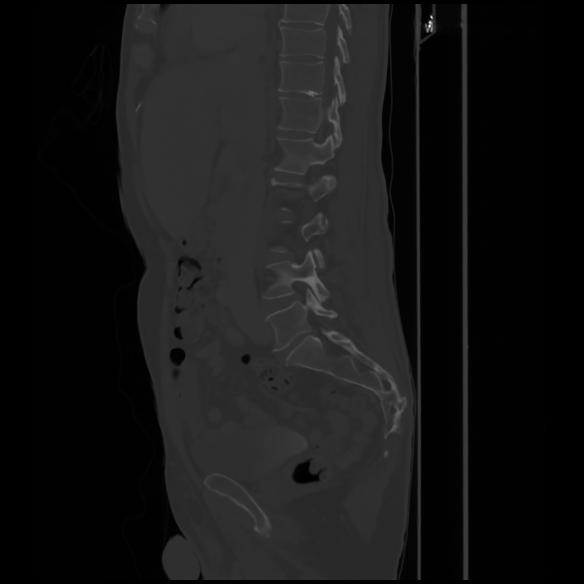

7 CUERPO,CE,Sagittal,3.000,CUERPO,Sagittal,